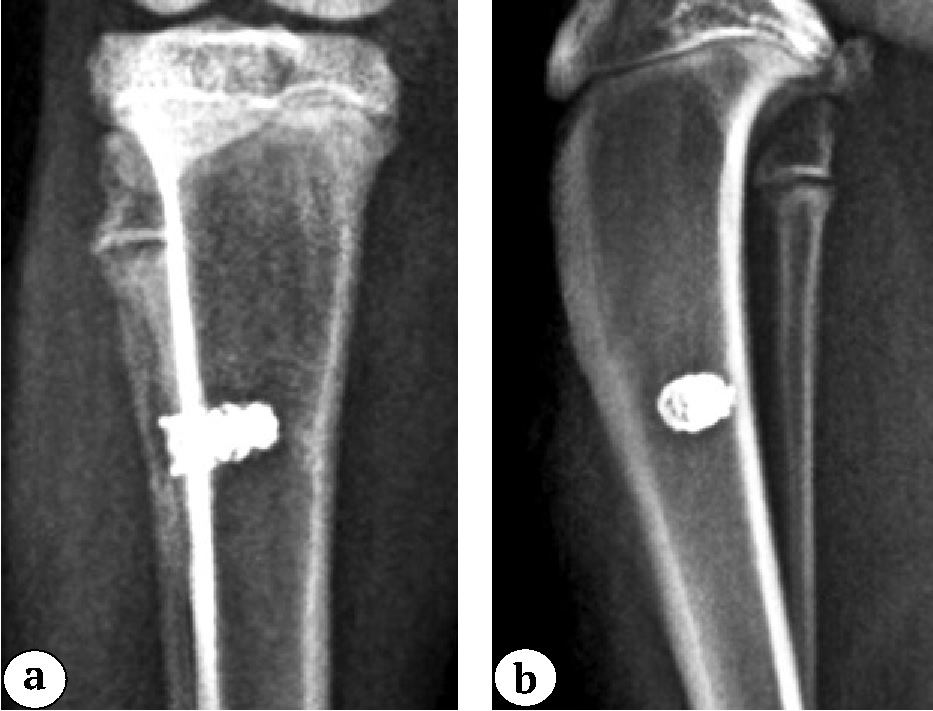

Имплантируемые изделия для одного и того же животного были идентичны. Контрольным рентгенологическим исследованием через 3 нед. после операции на установке Toshiba X-ray tube stand (DS-TA-5A) была подтверждена правильная установка имплантатов в ПОБК (рис. 2).

Рис. 2 (a, b). Рентгенограммы проксимального отдела бедренной кости кроликов через 4 нед. после имплантации 3D-имплантатов: а, b — титан без модификации поверхности

Figure 2 (a, b). X-rays of the proximal tibia of rabbits 4 weeks after integration of 3D-printed implants: a, b — titanium without surface modification